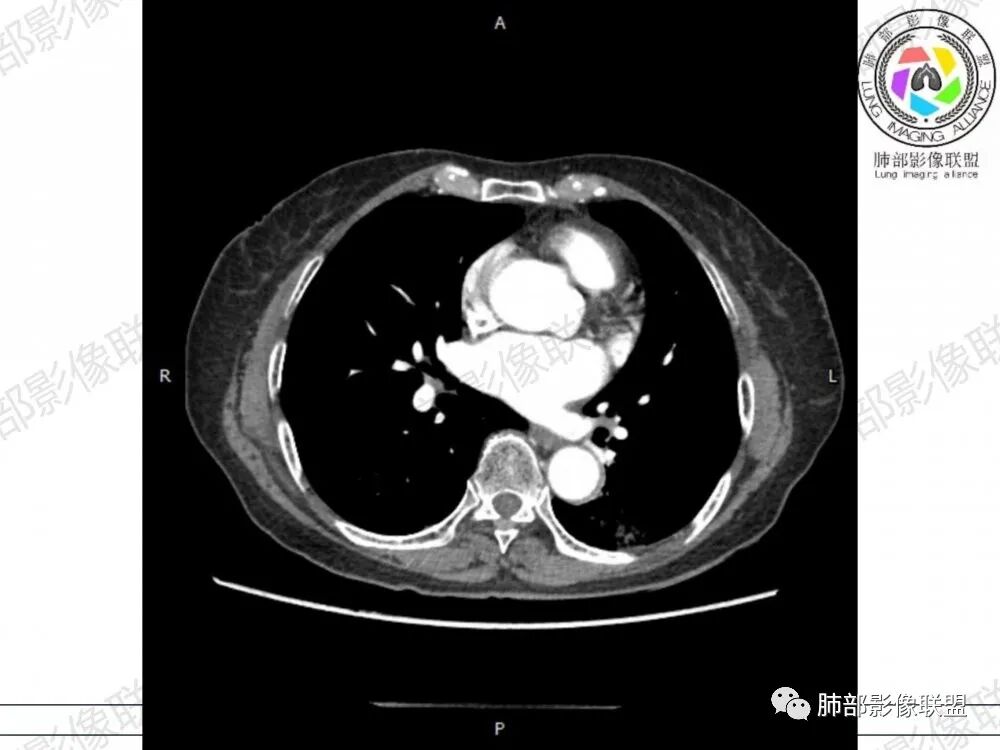

晨读病例,老年人男性 左肺下叶病灶,实性病变加上边界清晰的磨玻璃影,实性病变可见明显的膨胀性生长,增强实性部分可见血管照影征,考虑腺癌,粘液腺癌可能。

左肺下叶胸膜下混合磨玻璃影,磨玻璃边界清晰,支气管进入后堵塞,增强轻中度强化,无明显坏死空洞。

空腔+铺路石征+边界清楚GGO+病灶内血管局部扭曲+强化不均匀+病史长,指向腺癌,特别是粘液腺癌

晨读:左肺下叶胸膜下实性高密度影,部分伴有网格样增厚,内部可见小空泡,壁光滑,周围伴有磨玻璃影,边界清,近端可见支气管穿行,远端支气管堵塞,胸膜下脂肪间隙可见,病变整体收缩,部分有彭隆,增强后可见血管穿行,强化尚均匀。

左肺下叶实变及磨玻璃影,宽基底与胸膜相远,磨玻璃边界清晰,边缘膨隆,病变内近端支气管堵塞,不均匀强化,可见血管影,考虑腺癌,鉴别结核

胸CT:左下叶胸膜下大片斑片影,长轴沿胸膜分布,实变、GGO混杂,磨玻璃边界清晰,粘液密度,小叶内间隔增厚,支气管进入后堵塞(枯枝),增强轻中度强化,血管造影征。常规考虑:肺腺癌?淋巴瘤?鉴别不典型病原体感染。

周围GGO,呈碎石路征,边界清楚

主体病灶

2、影像表现:无肺气肿背景,病变定位于左肺下叶背内侧基底段,病灶呈不规则团块影,靠近胸膜侧,其内密度不均匀,内见空洞、实变及磨玻璃影,磨玻璃影呈碎石路征,边界清楚,实性肿块边界膨隆,其内见空洞。空洞周围比较实。病灶较大的支气管通畅,细小的支气管成“枯枝征”。无胸膜增厚及胸膜腔积液,增强扫描呈中度强化,见血管造影征。